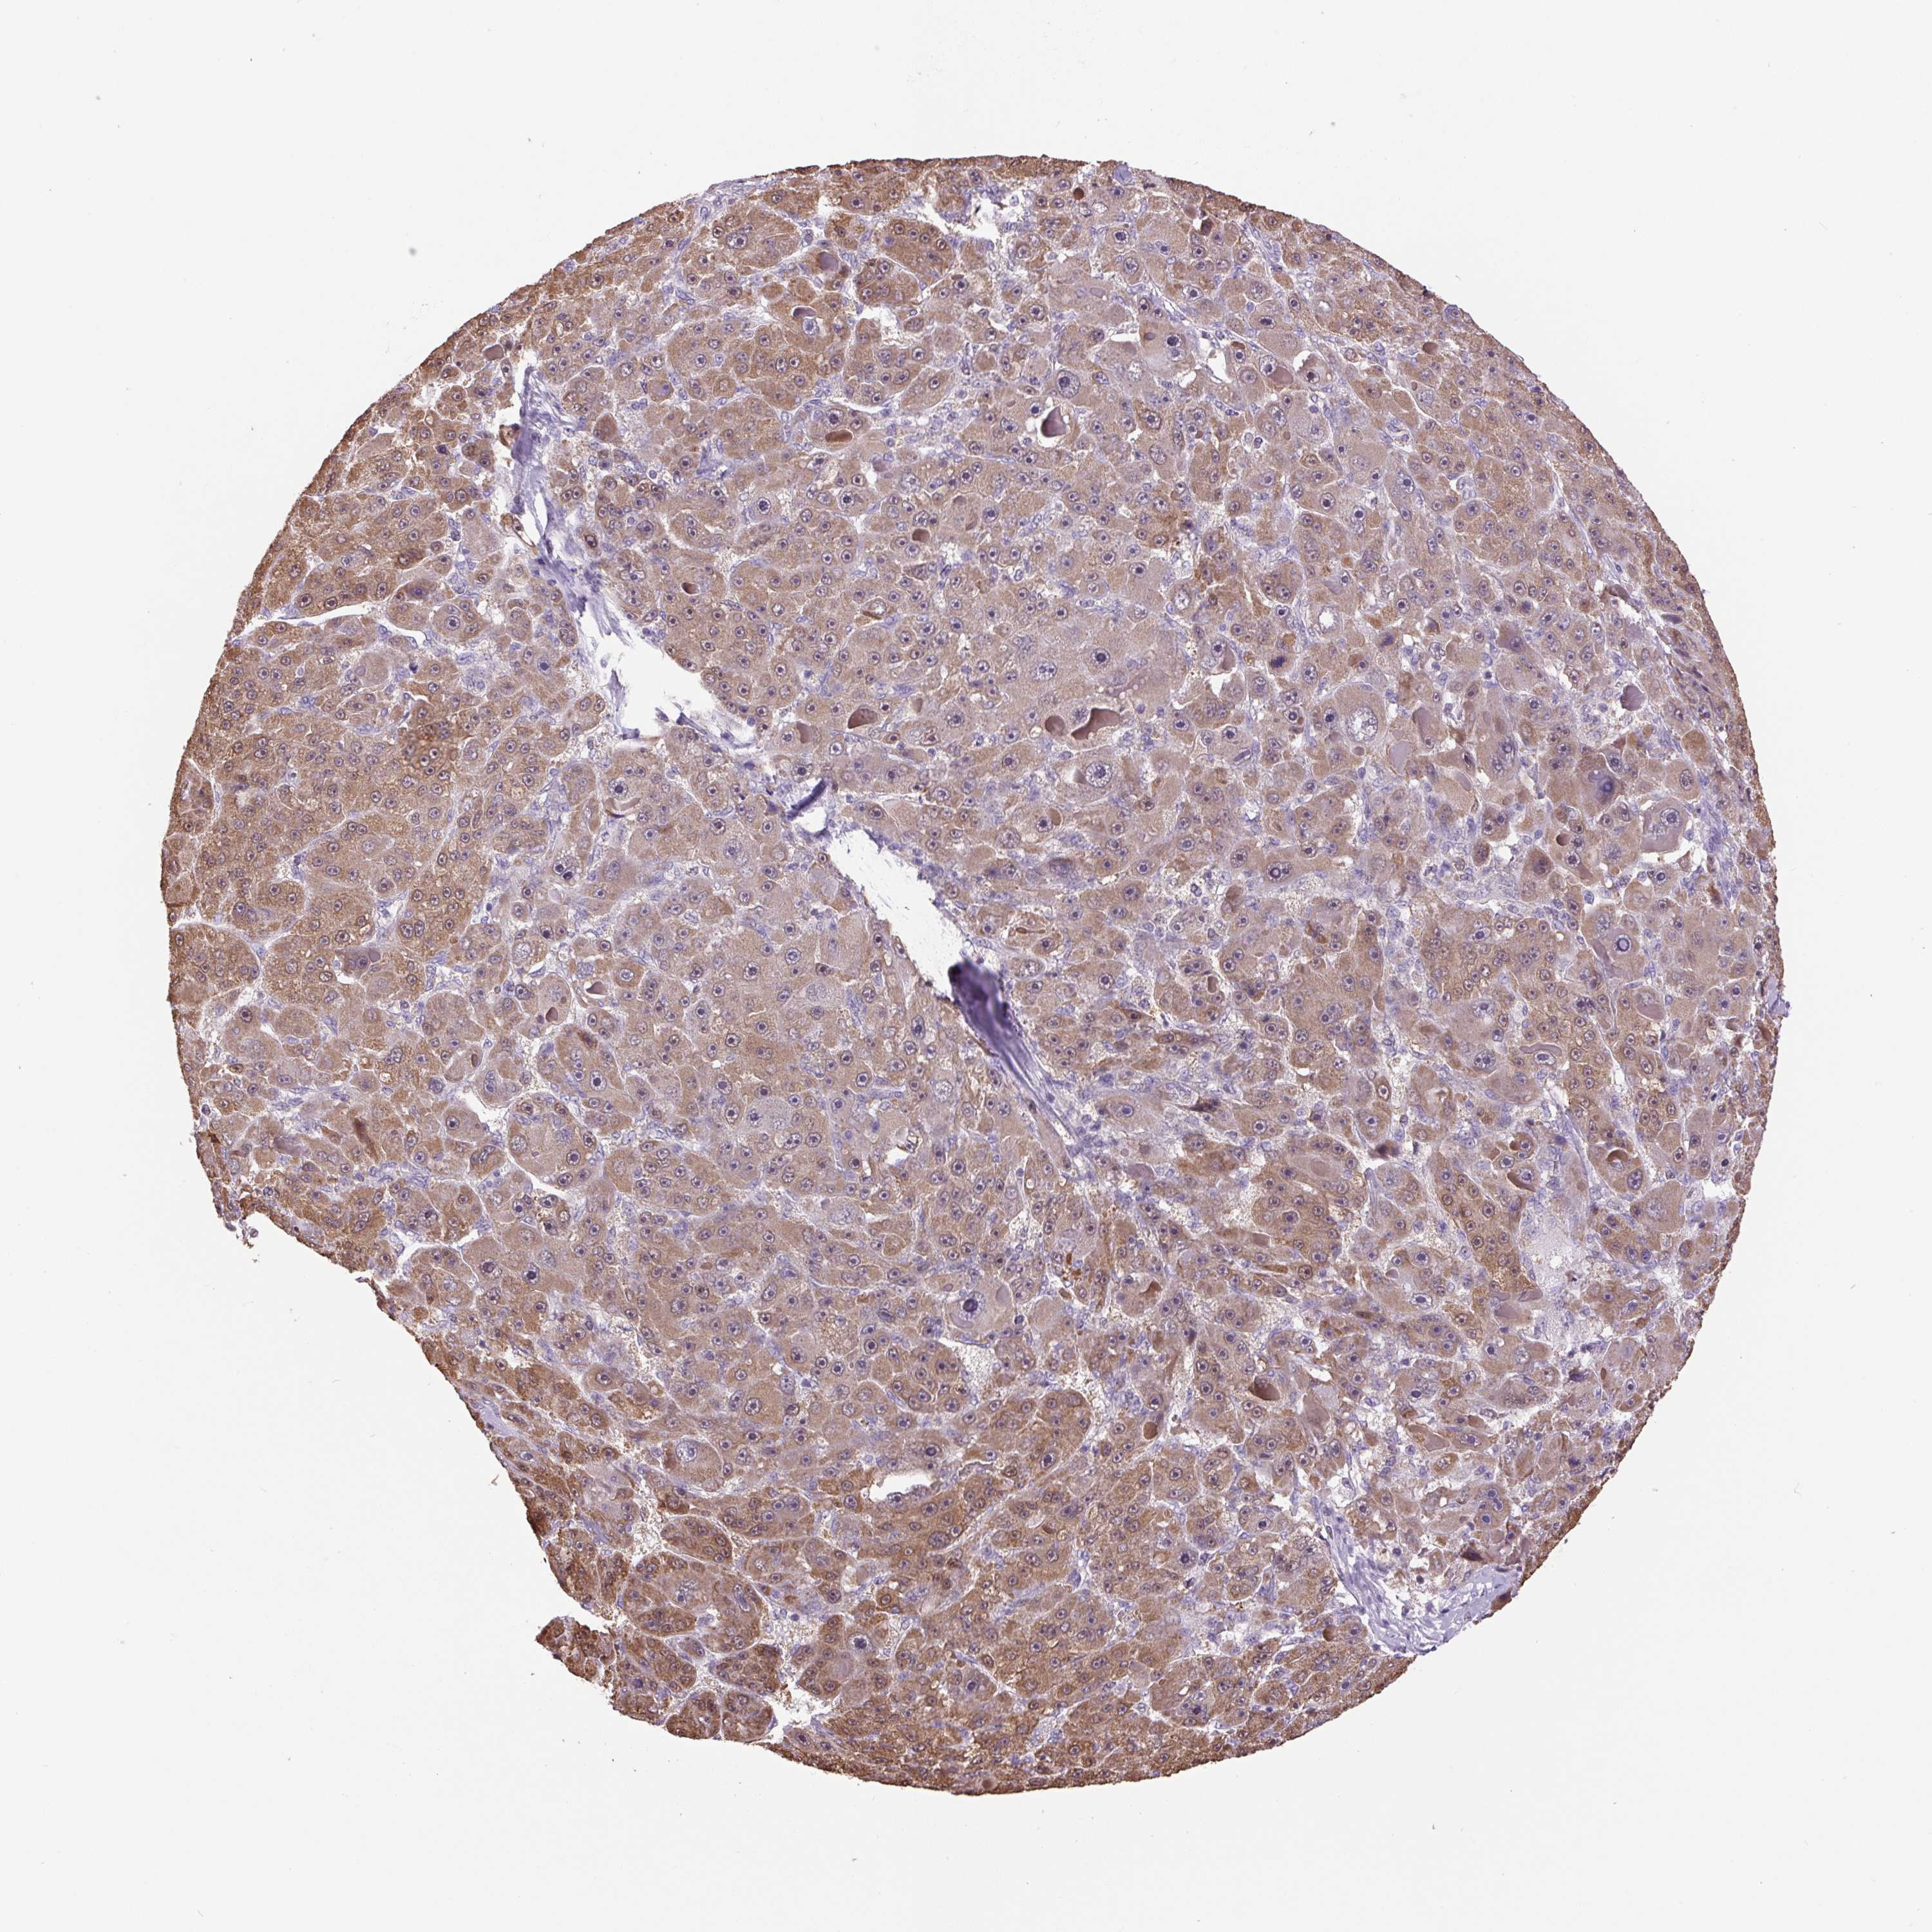

LIVER CANCER - Protein expressioni

A mouse-over function shows sample information and annotation data. Click on an image to view it in a full screen mode. Samples can be filtered based on level of antibody staining by selecting one or several of the following categories: high, medium, low and not detected. The assay and annotation is described here.

Note that samples used for immunohistochemistry by the Human Protein Atlas do not correspond to samples in the TCGA dataset.

Antibody stainingi

Antibody staining in the annotated cell types in the current human tissue is reported as not detected, low, medium, or high, based on conventional immunohistochemistry profiling in selected tissues. This score is based on the combination of the staining intensity and fraction of stained cells.

Each image is clickable and will lead to virtual microscopy that enables deeper exploration of all samples and also displays staining intensity scores, fraction scores and subcellular localization as well as patient and tissue information for each sample.

Antibody HPA052590

Antibody HPA053608

Staining

High

Cholangiocarcinoma

Carcinoma, Hepatocellular, NOS